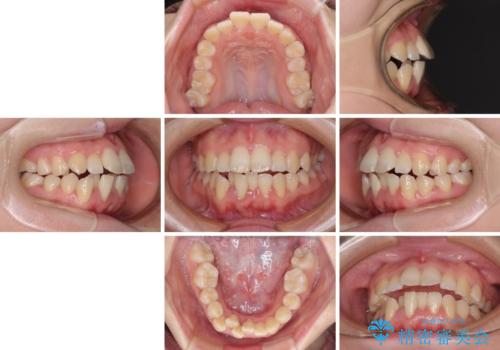

上下非接触で突出した前歯 ワイヤー装置による抜歯矯正

- 上下前歯の隙間と口元の出っ張った感じを気にして来院された患者様です。

上下の隙間は舌突出癖によるもので、またその癖により前歯が前方に出ている状態でした。

口元の出っ張りを改善するため、上下左右第一小臼歯4本を抜去し、ワイヤー装置にて矯正治療を行うこととしました。

舌の突出癖を改善するためのトレーニングをしっかりと行っていただいたことで、比較的スムーズに治療を進めることができました。

口元の突出感もしっかりと改善することができました。